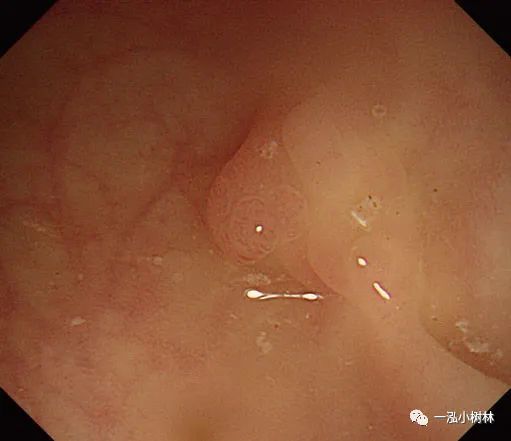

二、冷圈套息肉切除术

1.冷圈套息肉切除术(Cold snare polypectomy,CSP)是一种安全、有效的内镜下切除小息肉(小于10mm大小)的方法,但这一技术是理想的适应证是4~6mm大小的无蒂息肉。CSP与电切法相比,不存在潜在的穿孔风险。大小在10~13mm的圆形隆起息肉完全适合CSP。

图片

图4a 小无蒂息肉的冷圈套息肉切除术

图4b 直肠5mm大小Is型无蒂腺瘤

图4c 同一病变的NBI图像

图4e 圈套病灶包括周围1-2mm正常黏膜

图4f 切除标本保留在息肉切除部位

图4 g息肉摘除术后创面

2.最近的一项随机研究表明,在内镜下对小息肉的治疗中,CSP技术优于冷钳息肉切除术,并且在完整性和操作时间方面均优于冷钳息肉切除术。

3.将息肉边缘正常黏膜包括在内,用圈套器夹住并机械横切。切取的速度要快,因为慢的横切会造成黏膜下组织大量的损伤和随后不必要的出血。

4.下一个重要步骤是将息肉切除部位的标本通过结肠镜钳道吸入。切除息肉后,应将结肠镜头指向切除部位,随后吸引。

5.CSP技术可能导致息肉切除失败和黏膜出血。在最近的随机试验中,息肉的切除率是93.2%~96.0%。在不服用抗血小板药物或抗凝剂的患者中,大多数黏膜出血是自行停止的,没有明显出血的危险。